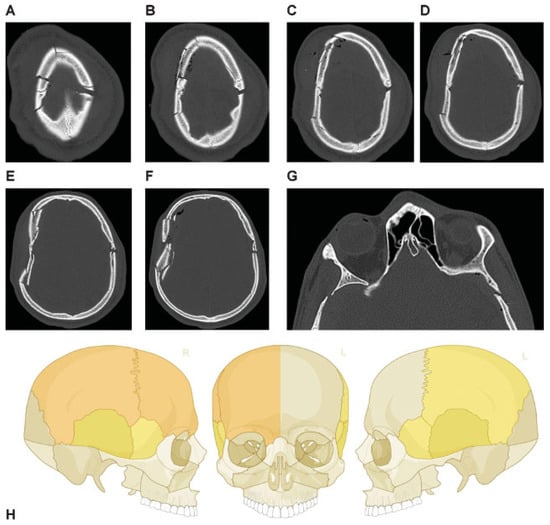

This coding system allows description of most relevant fracture patterns as illustrated in the case examples, such as the differentiation between unilateral or bilateral fracture patterns. In a series of three case examples, we illustrate the coding of a case with multiple cranial vault fractures (Figure 5), a single skull base fracture extending into the temporal cranial vault (Figure 6) and a right occipital and temporal cranial vault fracture extending into right middle fossa skull base (Figure 7). A range of additional fracture patterns are presented in a special case appendix as electronic supplement to this issue of the Journal (www.aocmf.org/classification).

Figure 7. Right occipital and temporal cranial vault fracture extending into the right middle fossa skull base. (A–C) Right occipital cranial vault fracture extending inferiorly into the right temporal bone, (D–H) with extension across the right middle fossa skull base through the skull base portion of the right temporal bone. There does not appear to be any fragmentation. (D) A probable left sphenoid fracture may be noted as well. Imaging: Computed tomographic axial views. (I) Level 3 code: 93 T0.M0.m.S, 94 O0.m, This case example CMTR-93-94-003 is made available electronically for viewing using the AOCOIAC software at www.aocmf.org/classification.